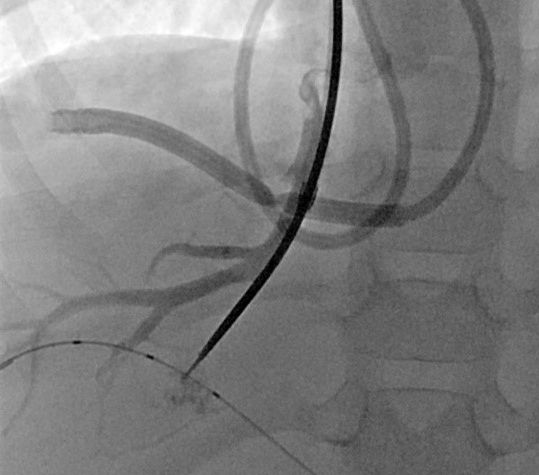

3- jähriger Junge mit stattgehabter Pfortaderthrombose (Verschluss der Pfortader).

Zustand nach Anlage eines Meso-Rex Shunts. Aktuell Größenzunahme der Milz und zunehmende Zeichen des Pfortaderhochdrucks. Sonographisch wurde dann der Verdacht auf eine Stenose (Verengung) der Shunts gestellt. In der Angiographie mit einem Zugang über Milz zeigte sich die vermutete Stenose (Pfeil in Bild A). Es wurde dann ein Stent eingebracht und mittels Ballon dilatiert (B). In der Kontrolle zeigte sich ein gutes Ergebnis mit Beseitigung der Engstelle. Dem Patienten ging es rasch besser.